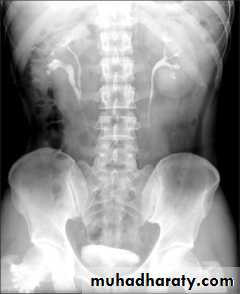

Horse shoe kidney -Kidneys may fail to separate.

-Almost invariably the lower poles remain fused.

-The kidneys axes are more parallel to the spine and malrotated.

-Diagnosis can be made by plain x-ray in some cases.

-US, CT scan and MRI can better demonstrate the anatomy and morphology hence the diagnosis.

-May be an incidental finding.

-PUJ obstruction and calculi formation are common .

IVU shows

1. The kidneys at low position .

2.Close to the spine with long axis parallel to the spine .

3. Malrotation manifested by medially directed calyces.

4- The renal pelvis and ureters are anterior and lateral in position .